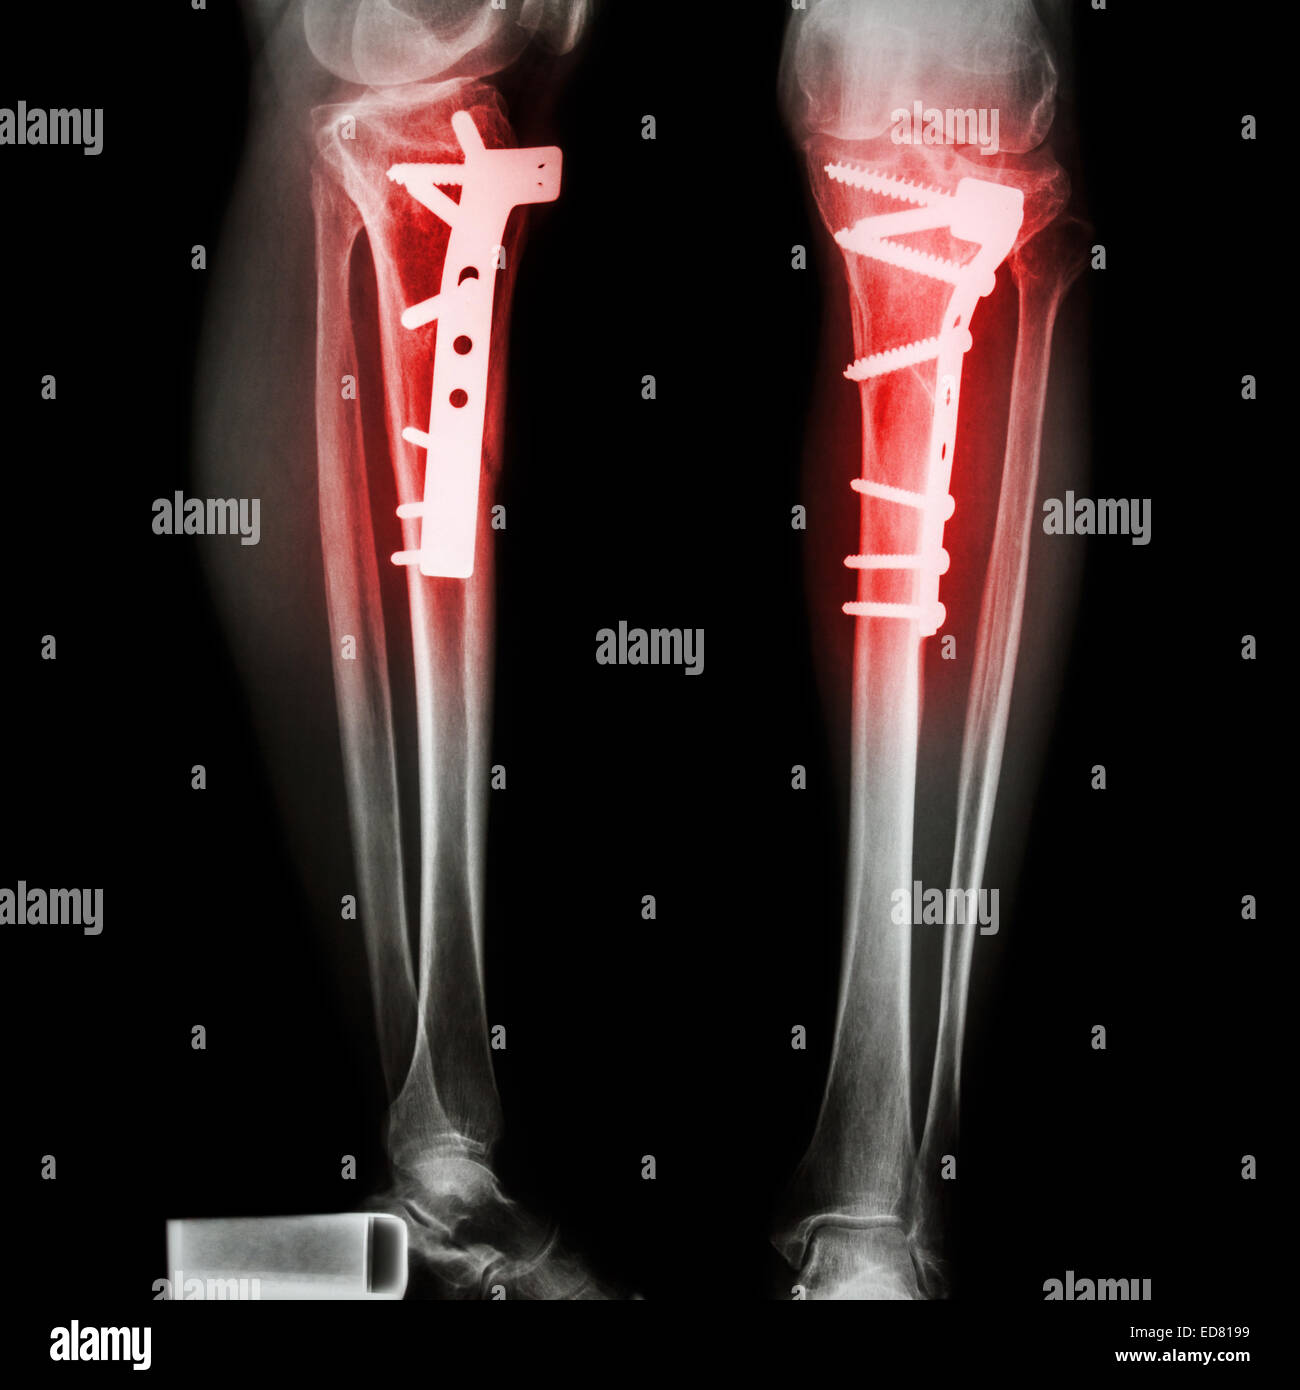

Tibia fracture de jambe(os). Il a été exploité et internes fixés par vis-plaque Banque D'Imageshttps://www.alamyimages.fr/image-license-details/?v=1https://www.alamyimages.fr/photo-image-tibia-fracture-de-jambe-os-il-a-ete-exploite-et-internes-fixes-par-vis-plaque-77395834.html

Tibia fracture de jambe(os). Il a été exploité et internes fixés par vis-plaque Banque D'Imageshttps://www.alamyimages.fr/image-license-details/?v=1https://www.alamyimages.fr/photo-image-tibia-fracture-de-jambe-os-il-a-ete-exploite-et-internes-fixes-par-vis-plaque-77395834.htmlRFEDWK4X–Tibia fracture de jambe(os). Il a été exploité et internes fixés par vis-plaque

Tibia fracture de jambe(os). Il a été exploité et internes fixés par vis-plaque Banque D'Imageshttps://www.alamyimages.fr/image-license-details/?v=1https://www.alamyimages.fr/photo-image-tibia-fracture-de-jambe-os-il-a-ete-exploite-et-internes-fixes-par-vis-plaque-77008661.html

Tibia fracture de jambe(os). Il a été exploité et internes fixés par vis-plaque Banque D'Imageshttps://www.alamyimages.fr/image-license-details/?v=1https://www.alamyimages.fr/photo-image-tibia-fracture-de-jambe-os-il-a-ete-exploite-et-internes-fixes-par-vis-plaque-77008661.htmlRFED8199–Tibia fracture de jambe(os). Il a été exploité et internes fixés par vis-plaque

Tibia fracture de jambe(os). Il a été exploité et internes fixés par vis-plaque Banque D'Imageshttps://www.alamyimages.fr/image-license-details/?v=1https://www.alamyimages.fr/photo-image-tibia-fracture-de-jambe-os-il-a-ete-exploite-et-internes-fixes-par-vis-plaque-77008659.html

Tibia fracture de jambe(os). Il a été exploité et internes fixés par vis-plaque Banque D'Imageshttps://www.alamyimages.fr/image-license-details/?v=1https://www.alamyimages.fr/photo-image-tibia-fracture-de-jambe-os-il-a-ete-exploite-et-internes-fixes-par-vis-plaque-77008659.htmlRFED8197–Tibia fracture de jambe(os). Il a été exploité et internes fixés par vis-plaque

Tibia fracture de jambe(os). Il a été exploité et internes fixés par vis-plaque Banque D'Imageshttps://www.alamyimages.fr/image-license-details/?v=1https://www.alamyimages.fr/photo-image-tibia-fracture-de-jambe-os-il-a-ete-exploite-et-internes-fixes-par-vis-plaque-77008660.html

Tibia fracture de jambe(os). Il a été exploité et internes fixés par vis-plaque Banque D'Imageshttps://www.alamyimages.fr/image-license-details/?v=1https://www.alamyimages.fr/photo-image-tibia-fracture-de-jambe-os-il-a-ete-exploite-et-internes-fixes-par-vis-plaque-77008660.htmlRFED8198–Tibia fracture de jambe(os). Il a été exploité et internes fixés par vis-plaque